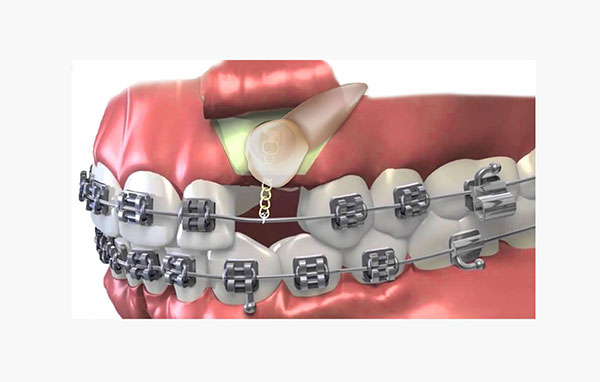

درمان نیش نهفته با ارتودنسی

جهت درمان نهفتگی دندان نیش می توان از ارتودنسی ثابت استفاده کرد. در این صورت یک جراحی ساده مورد نیاز است تا دندان نیش نمایان شود. سپس با نصب براکت ارتودنسی روی دندان، با زنجیر مینیاتوری به سیم ارتودنسی متصل می شود.

پس از مدتی می بایست مجددا نزد پزشک رفت تا توسط بند رابری به زنجیر، نیروی بیشتری ایجاد کند. با این روند درمان ارتودنسی، ناهنجاری دندان نهفته از حالت افقی به عمودی و در جای مناسب هدایت خواهد شد.

دوره درمان حدود یک سال به طول می انجامد. در پایان درمان، بیرون آمدن نهفتگی دندانی را مشاهده خواهید کرد.

جراحی و ارتودنسی دندان نیش نهفته

جراحی و ارتودنسی دندان نهفته یکی از شاخه های جراحی دهان و دندان می باشد. جراحی برای ظاهر ساختن دندان نهفته می بایست توسط جراح فک و نصب براکت توسط ارتودنتیست صورت گیرد.

معمولا این جراحی با بی حسی موضعی صورت می پذیرد. حدود 45 دقیقه جراحی و نصب براکت، به طول می انجامد. اگر هر دو دندان نیش در حالت نهفته قرار داشته باشند، این زمان بیشتر خواهد شد.